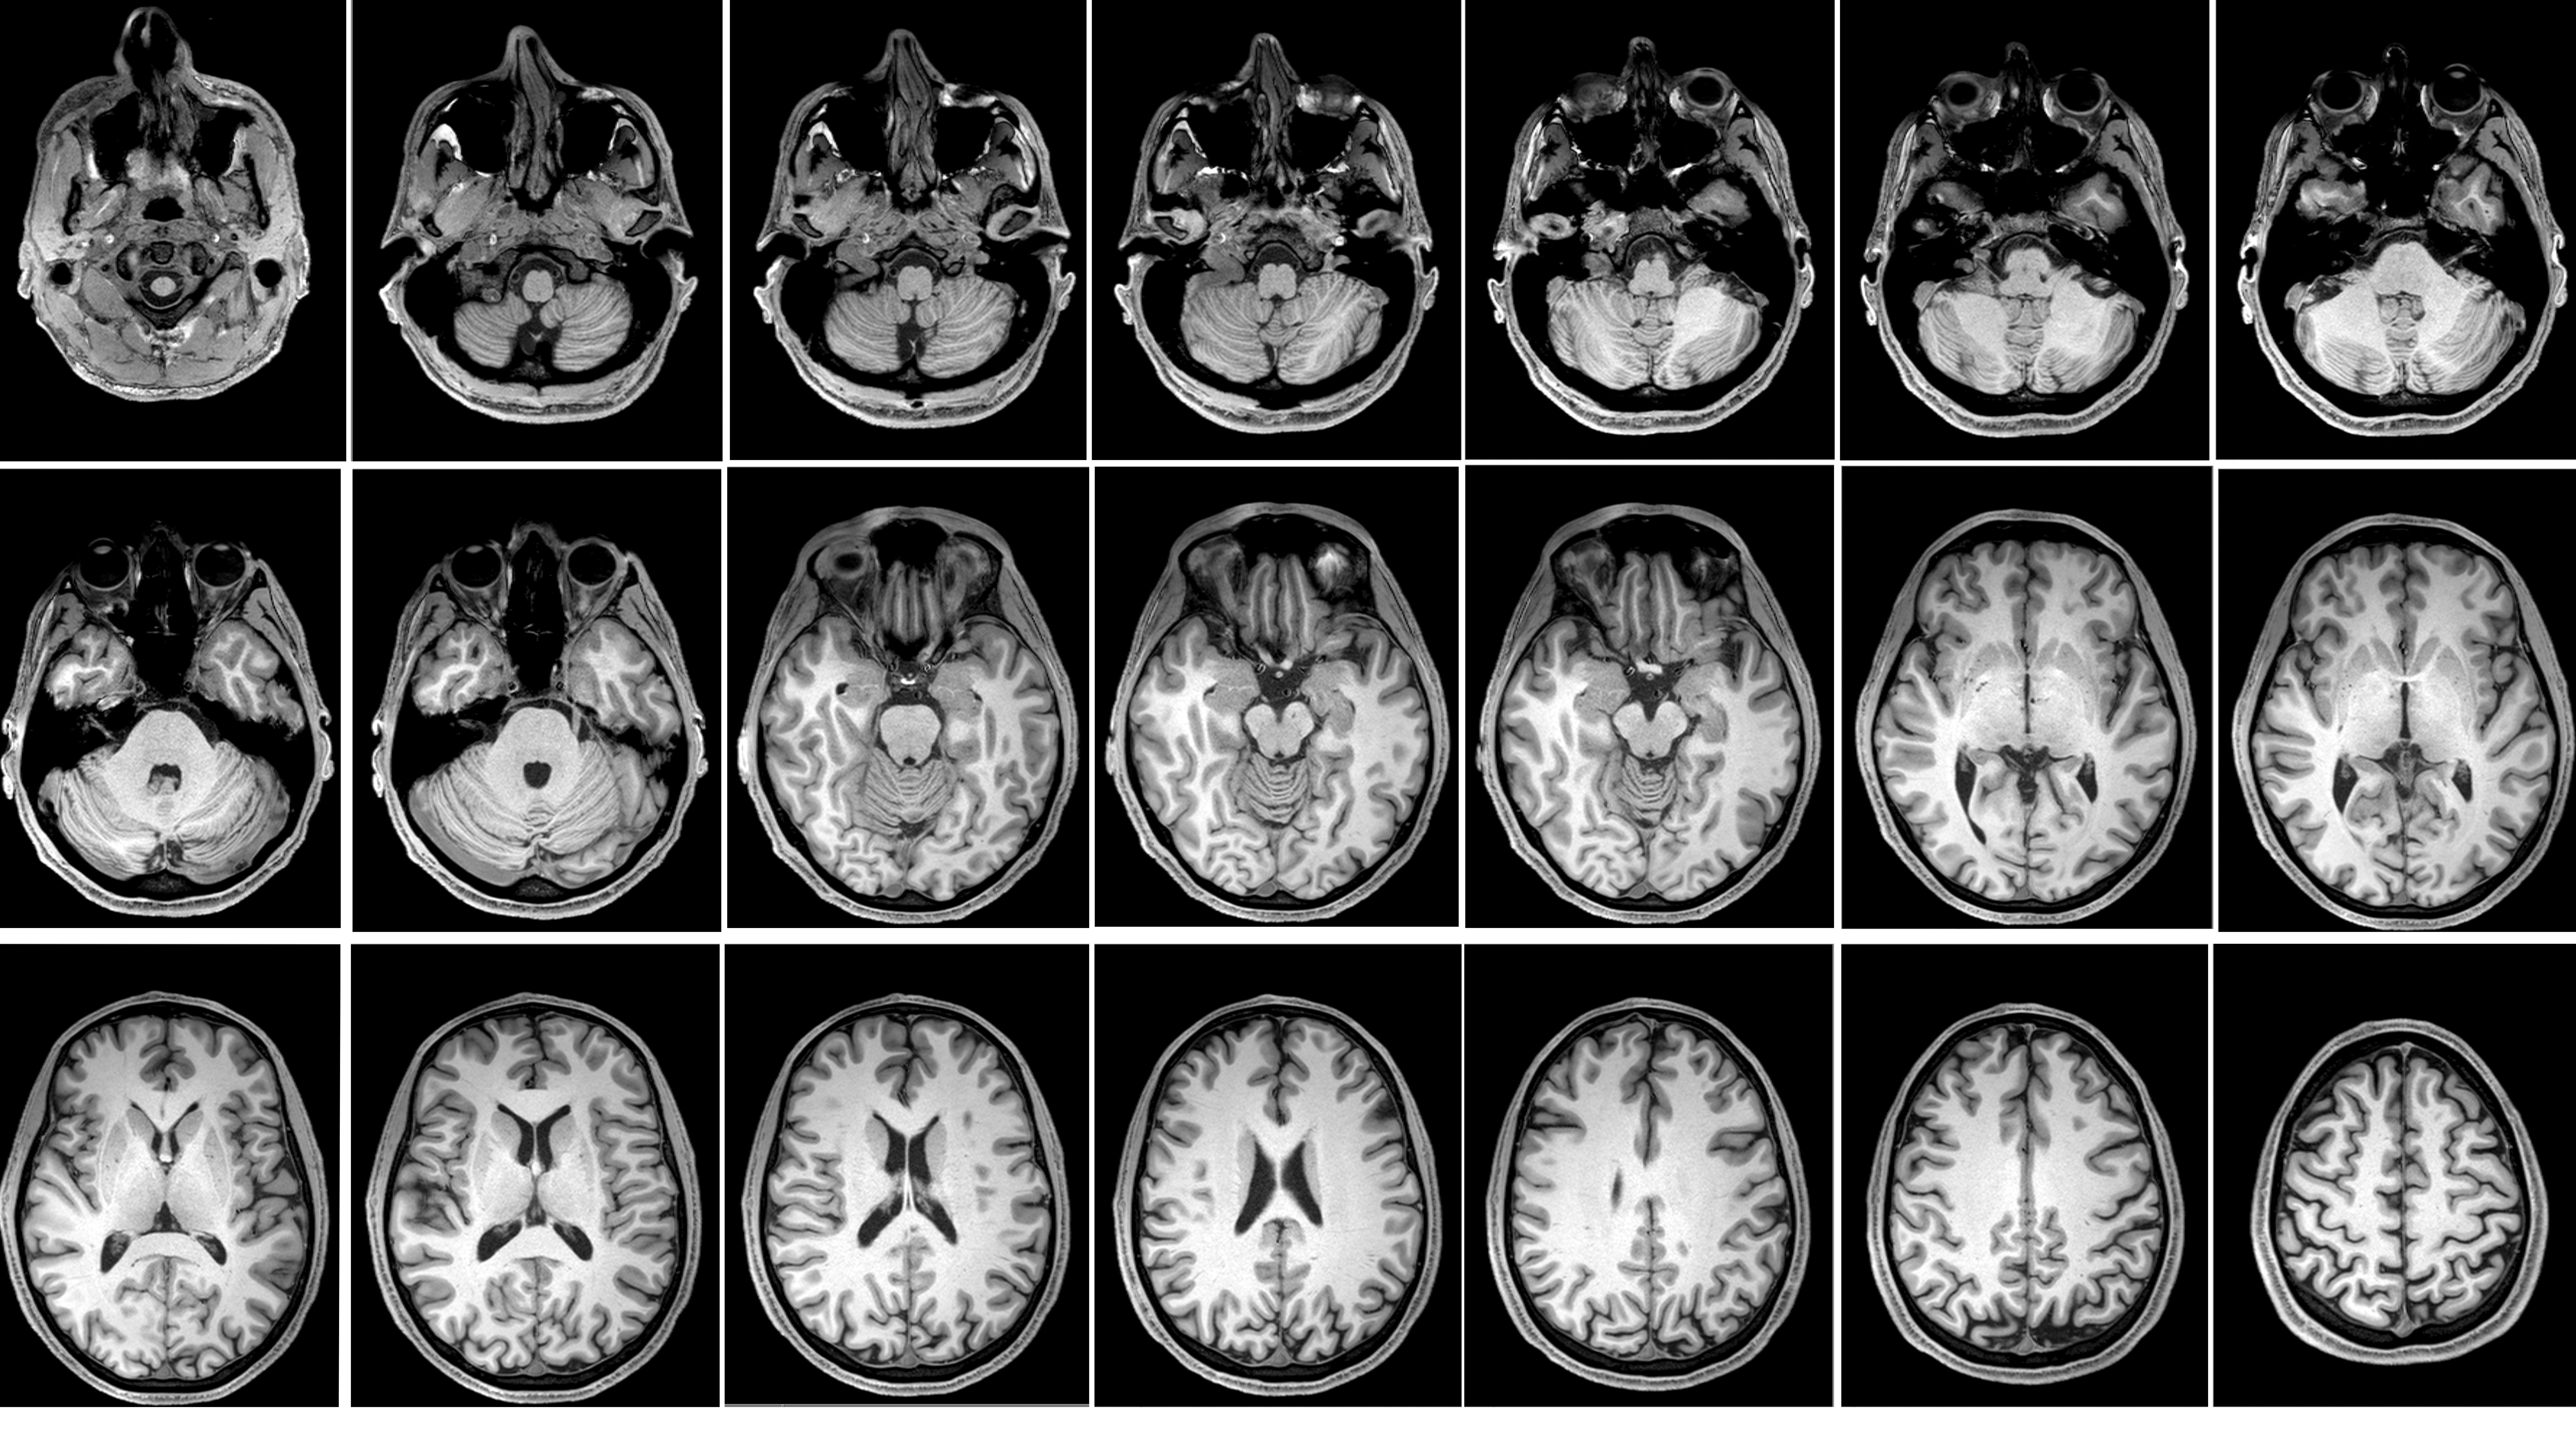

Au cours de cette unité, des travaux pratiques de neuro-anatomie sont organisés pour vous permettre d’appliquer votre savoir à l’aide de pièces anatomiques et d’images radiologiques.

Il est essentiel que vous veniez préparé.e.s à ces TP pour pouvoir en bénéficier au maximum. De plus, l’interactivité rend les TP de 4 heures moins longs et plus enrichissants. N’hésitez donc pas à participer, manipuler les pièces, poser vos questions, et participer aux dissections... À la fin de l’unité, vous devriez être à l’aise en naviguant dans le SNC et capables de mettre en lien l’anatomie des structures avec leur fonction.